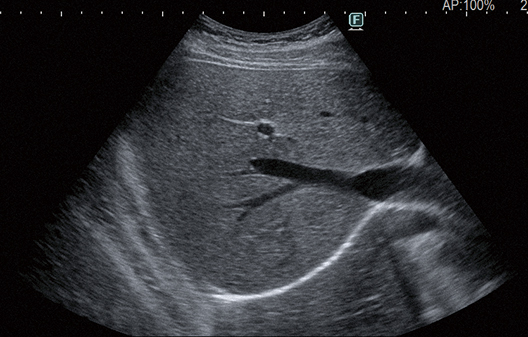

The eFocusing transmission and reception technology newly developed for ARIETTA 850, significantly improves S/N and reduces focal dependency. Outstanding clarity of imaging from near to far field with less patient dependency is achieved.

Focused at all depths

Advanced image technology producing images with "Clearer Visibility"*. Stable imaging with less patient dependency helps to achieve clearer images with less noise. This is made possible by our new image processing technology that enhances tissue structure visibility.